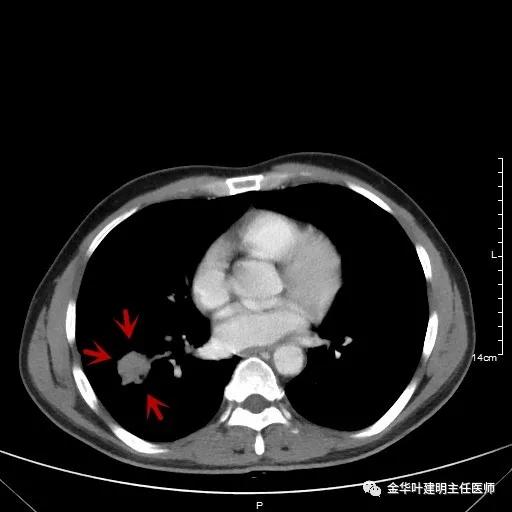

以上为纵隔窗,可见纵隔内未见显著增大的转移性淋巴结。